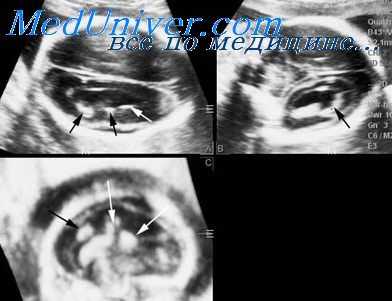

Акушерская тактика при тератоме шеи у плода

Локализация опухоли на передней поверхности шеи и ее частично солидная консистенция могут вызывать явления обструкции верхних дыхательных путей, что является самым ургентным состоянием в неонатологии, требующим немедленного принятия мер.

Когда это прогнозируется по результатам ультразвукового исследования, имеется возможность приготовить перед операцией кесарева сечения необходимое оборудование для устранения проблем с дыханием плода, если они возникнут. Хотя даже использование ларингоскопа и щипцов Мак Джила (McGill) и/или проволочного направителя интубационной трубки не всегда может помочь, в том числе и опытному неонатологу, преодолеть проблемы при интубации.

Чрезвычайная компрессия и изменение хода трахеи могут потребовать бронхоскопического контроля с целью предотвращения перфорации при этой манипуляции.

При небольших опухолях адекватную дыхательную вентиляцию может обеспечить выполнение экстренной трахеотомии. Повторные внутриутробные пункции с аспирацией содержимого кистозных компонентов опухоли, проводимые в антенатальном периоде, также могут снижать массу опухоли к моменту рождения и тем самым облегчить выполнение неонатальных хирургических вмешательств.

Более того, непосредственно перед родами такое пункционное дренирование кистозного компонента опухоли может уменьшить степень компрессии гортани и трахеи, что позволит успешно провести интубирование.

В одной из работ было предложено применять экстракорпоральную мембранную систему оксигенации крови путем катетеризации артерий и вен пуповины для поддержания гемоциркуляции у новорожденного. Такой подход дает время для оценки состояния гортани и трахеи без возникновения асфиксии у ребенка.

В случаях тяжелой обструкции временная оксигенация крови дает возможность провести немедленное хирургическое вмешательство в области шеи, для того чтобы обеспечить условия для адекватной вентиляции.

Ряд авторов считает полезным выполнять обследование с помощью магнитно-резонансной томографии (МРТ) и эхографии перед планированием операции, которую затем выполняют плоду во время кесарева сечения на фоне сохранения плацентарного кровообращения через пуповину в течение всего времени, необходимого для ее завершения.

Большие по размерам тератомы шеи, несмотря на редкую распространенность у плодов, повышают риск перинатальной смертности. После антенатальной диагностики таких состояний требуется мультидисциплинарный подход для определения акушерской тактики ведения и обеспечения неотложного решения дыхательных проблем, которые могут возникнуть сразу после рождения.